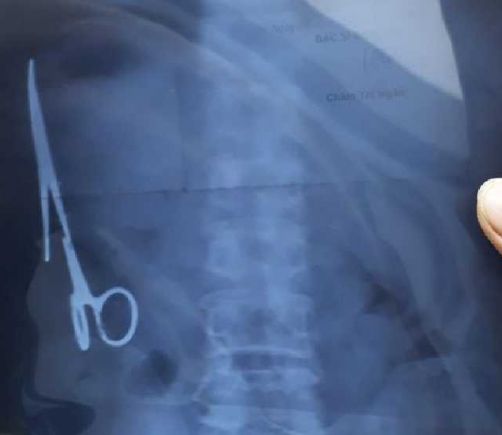

Extraen después de 20 años una tijera del abdomen de una mujer